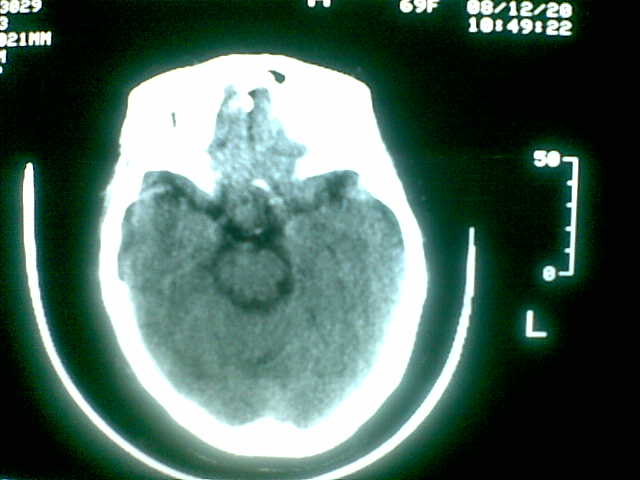

69岁 女 主因头痛就诊。大家看看起源于哪里啊

起源于斜坡,考虑脊索瘤.

考虑脊索瘤(起源于蝶枕联合部)。

颅底骨质破坏伴软组织密度影、斑片状高密度(死骨影)。

考虑:脊索瘤。

还要注意鼻咽部有没有什么问题,

考虑起源于斜坡的脊索瘤。血管瘤待排。